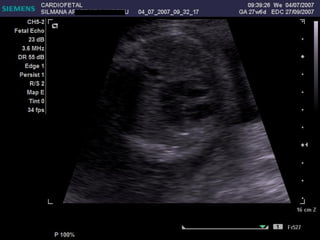

Cámaras COLUMNA AORTA ESTERNON VP VP BANDA MODERADORA FLAP VI VD AI AD

EXAMEN BASICO VENTRICULOS Tamaños Paredes Banda moderadora Tabique

Tamaño

Paredes

Banda moderadora

Tabique